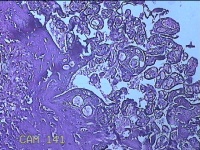

胎盘组织

孕2产39周LOP剖宫产单活胎男婴 剖宫产术

停经39周,下腹胀痛1小时。

灰白暗红色胎盘组织18x16x2.8㎝一个,表面光滑,血管清晰,颜色发暗,绒毛面结节状,轻度糜烂,表面有少许凝血块,切面见绒毛内有部分淤血,边缘蜕膜可见多个小血肿,脐带21.5x2x0.8㎝,切断脐带,见脐血管内有凝血块。